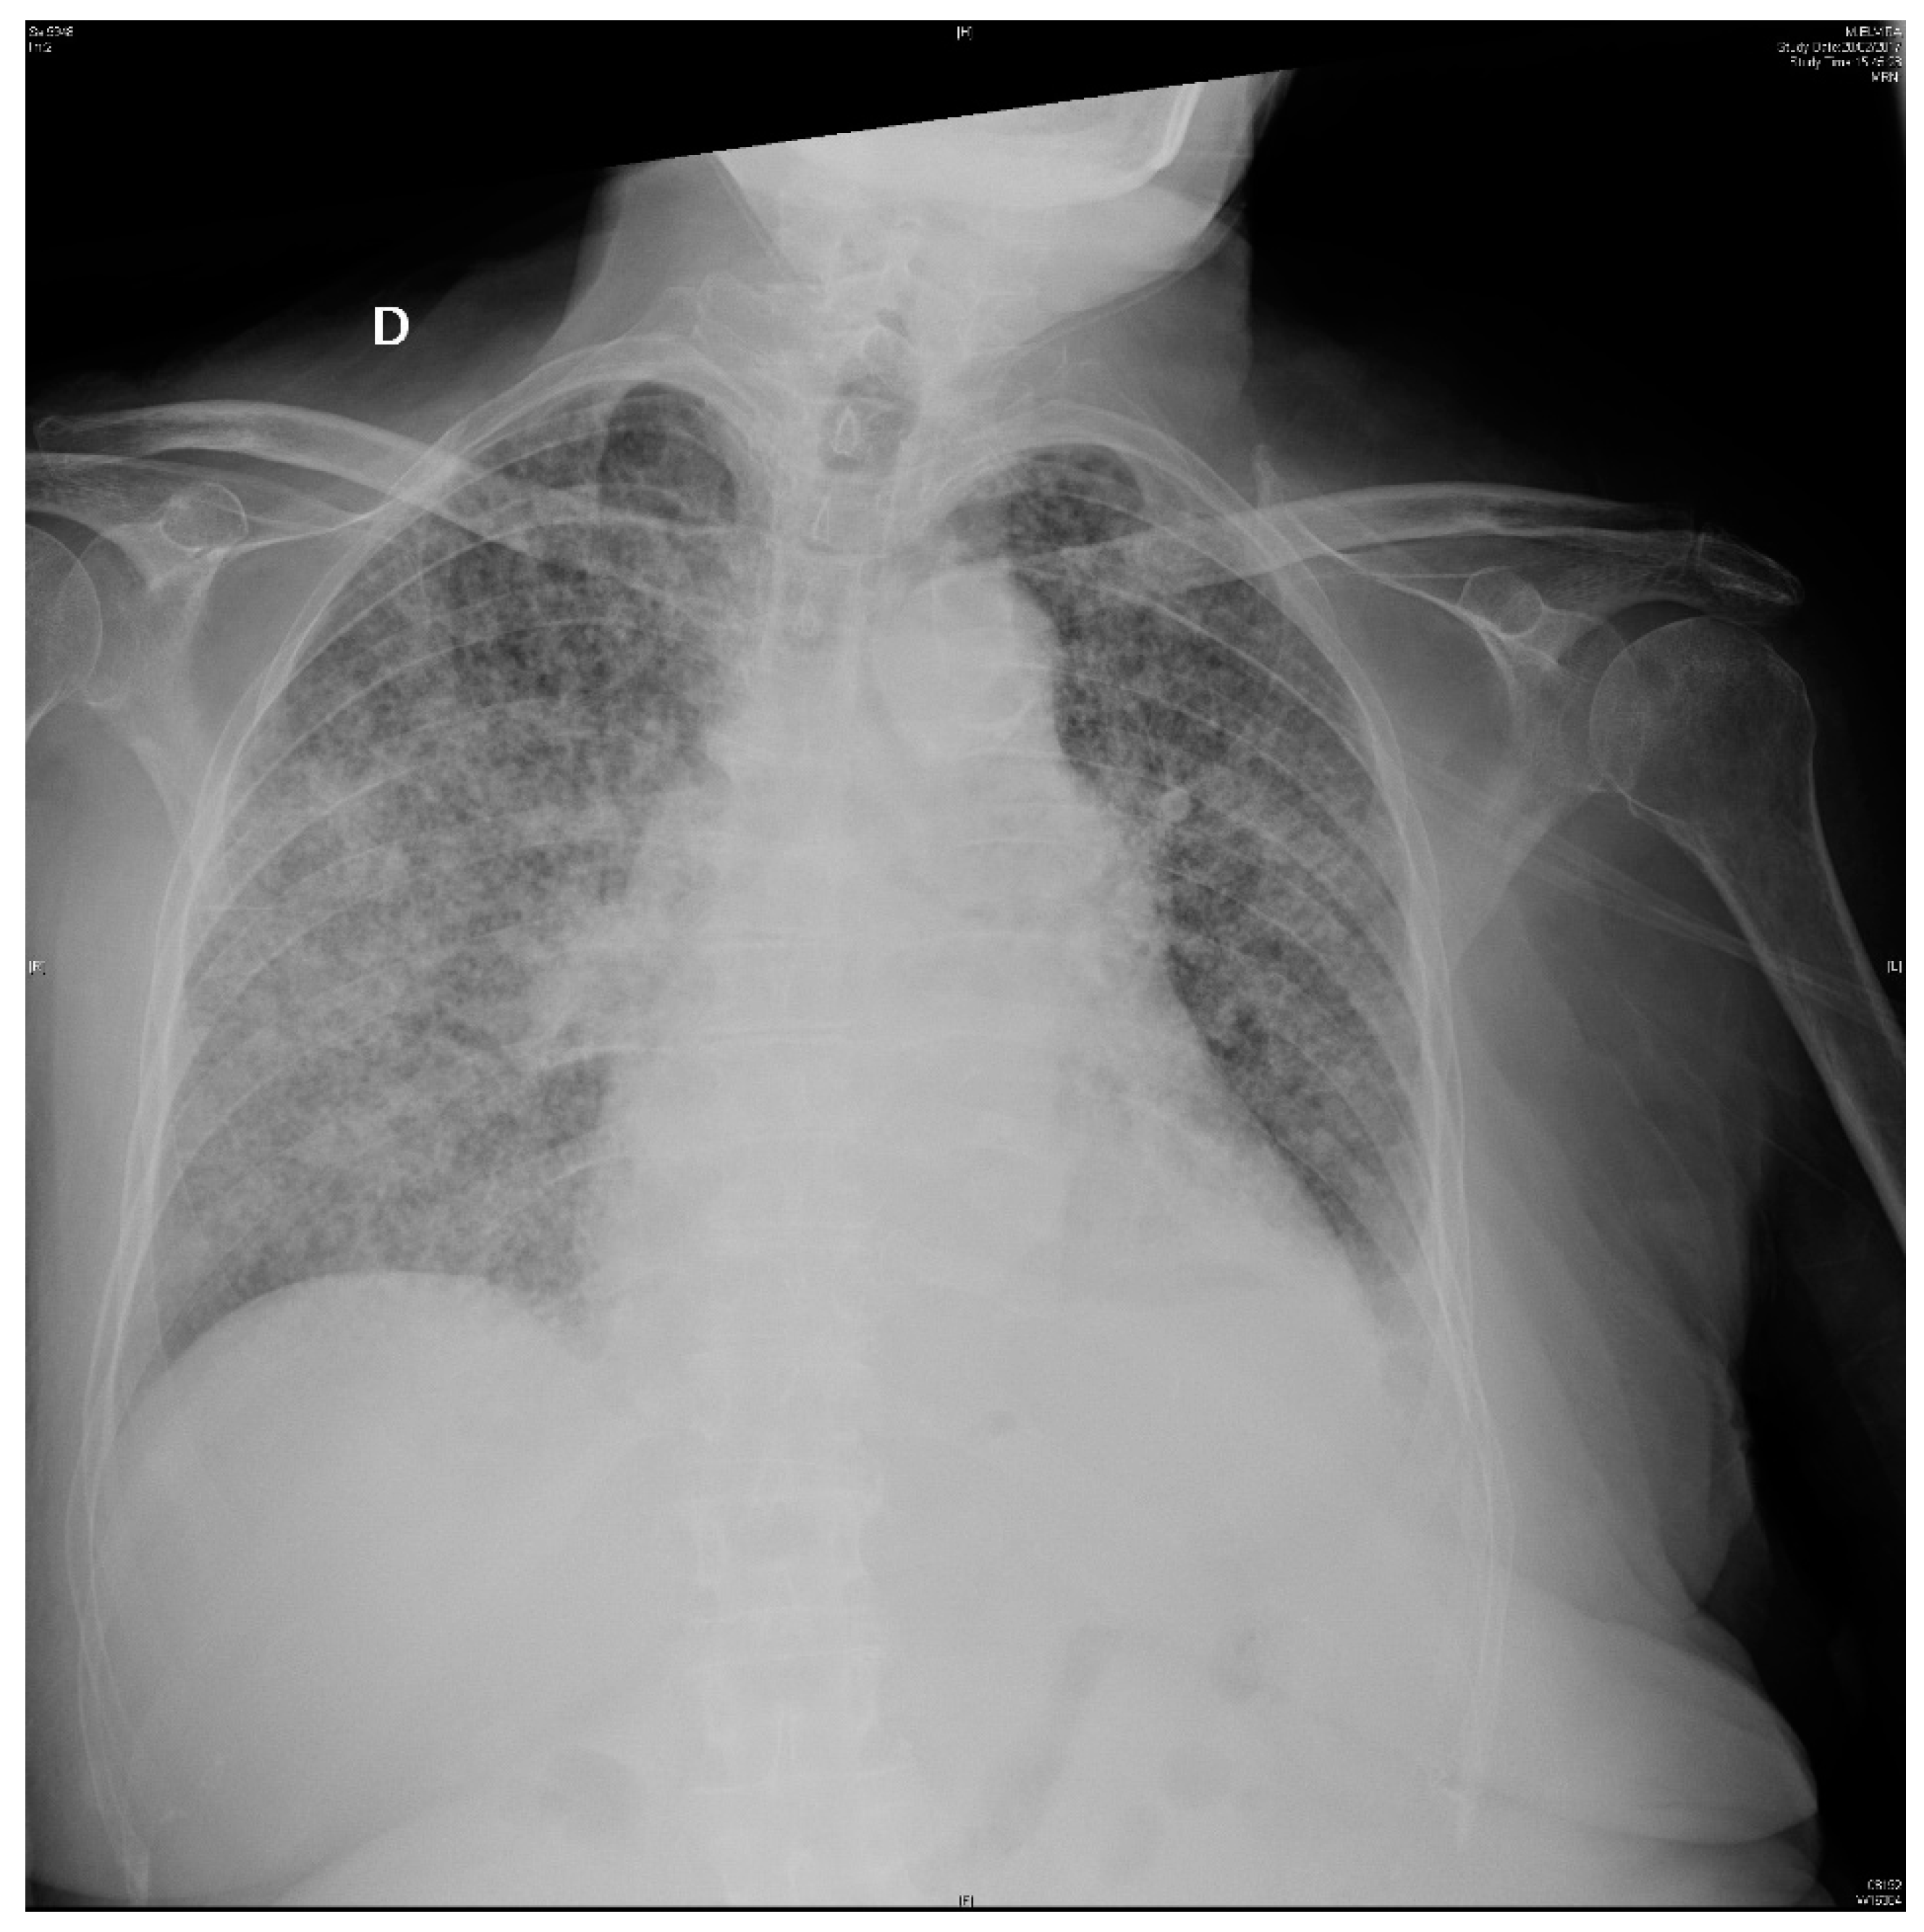

At admission, she was febrile (39 °C), eupneic with oxygen saturation 99%, a blood pressure of 125/85 mmHg, with a pulse rate of 86 bpm, arrhythmic, and a breath rate of 14 bpm. Physical exams revealed no abnormalities. At emergency department evaluation, laboratory work-up results were as follows: 6300 leukocytes with 80% neutrophils, erythrocytes count, platelets count, electrolytes and biochemistry tests were normal except for glycemia: 155 mg/dl, natremia: 123 nmol/L and C-reactive protein: 87 mg/dl. Urine analysis: 100 leukocytes and 10 erythrocytes per high-power field. Chest X-ray: normal without pulmonary infiltrates (Figure 1).

Figure 1.

Chest X-ray on admission: there are no infiltrates or opacities.